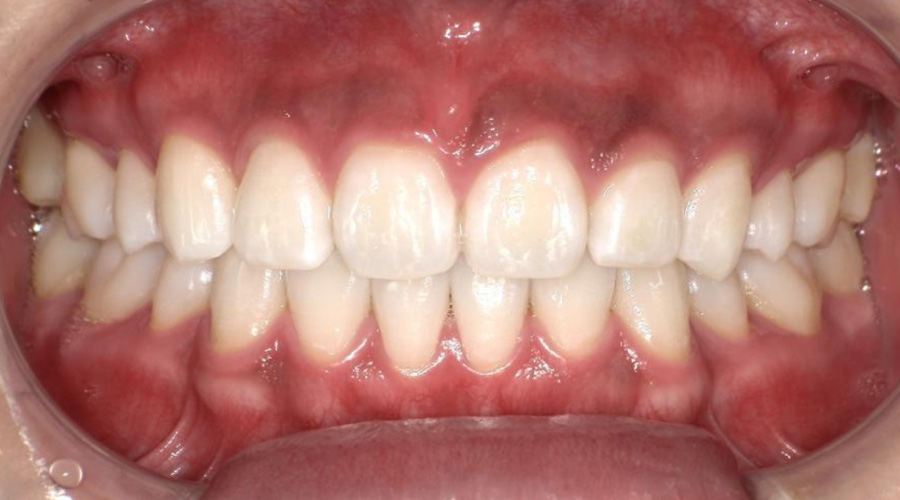

審美歯周病治療

見た目も美しく

歯周病治療を行うと歯茎が下がったとよく聞きます。残念ながら、炎症が長期に渡り存在していた歯茎や、重度歯周病では、治療を行うことにより歯茎が下がり炎症が除去されると歯茎が下がってしましやすいです。そういった場合、セラミックス治療を行うことで審美的に改善を図ることがあります。

また、歯周病はないのに、歯茎が下がってしまうことによる審美性が損なわれてしまう病気があります。そのような場合、歯茎の移植などを行うことにより、歯を削ることなく審美性を改善させることができます。 -